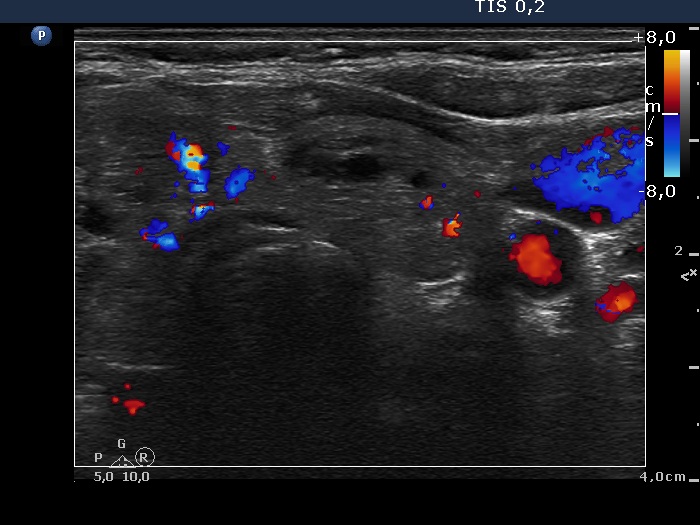

Right lobe, longitudinal scan

Left lobe, transverse scan, color Doppler mode. The vascularization is a bit increased.